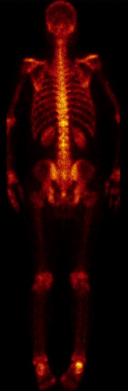

骨转移部位病灶消失,见下图,转移灶消失

2019-07-19放疗后复查全身骨扫描